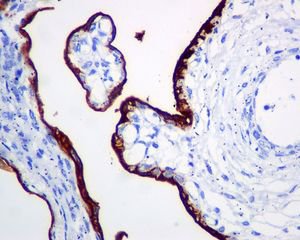

Immunohistochemistry (Formalin/PFA-fixed paraffin-embedded sections) - HRP Anti-ALPP+ALPG+ALPI antibody [EPR6141] (AB198554)

IHC image of Placental alkaline phosphatase (PLAP) staining in a section of formalin-fixed paraffin-embedded normal human placenta*, performed on a Leica BOND. The section was pre-treated using heat mediated antigen retrieval with sodium citrate buffer (pH6, epitope retrieval solution 1) for 20mins. The section was then incubated with ab198554 at 1/1000 dilution for 15 mins at room temperature. DAB was used as the chromogen. The section was then counterstained with haematoxylin and mounted with DPX. The inset negative control image is taken from an identical assay without primary antibody.

For other IHC staining systems (automated and non-automated) customers should optimize variable parameters such as antigen retrieval conditions, primary antibody concentration and antibody incubation times.

*Tissue obtained from the Human Research Tissue Bank, supported by the NIHR Cambridge Biomedical Research Centre